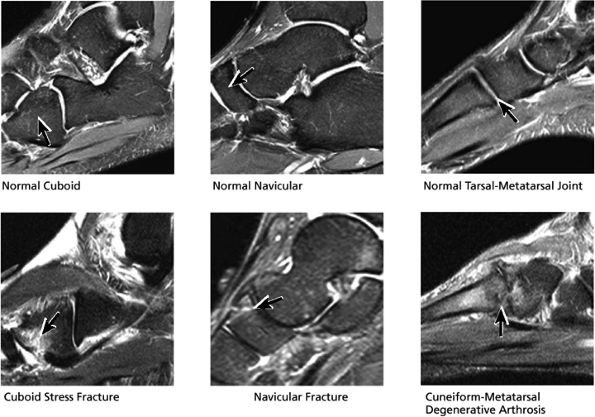

FIGURE 5.26 ● Coronal anatomy of the ankle and foot. (A) The calcaneofibular ligament (CFL) is identified by finding its origin at the inferior tip of the lateral malleolus. The posterior inferomedial course of the CFL is followed on three or four consecutive coronal images moving posteriorly through the ankle, to its insertion on the posterolateral calcaneus. Optimal evaluation of the CFL involves examining its full course on successive images in both the coronal and sagittal plane for tears, sprain, or scarring. (B) The medial cord of the plantar aponeurosis is normally slightly thicker than the lateral cord, and this mild asymmetry in thickness should not be misinterpreted as plantar aponeurosis scarring or plantar fasciitis. On successive coronal images, the course of the plantar aponeurosis should be followed back to its insertion on the inferior calcaneus and evaluated for the presence of thickening, decreased signal suggestive of scarring, increased signal indicative of plantar fasciitis, and tears. (C) Coronal images are optimal for viewing the lateral process of the talus, which is a frequent site of fractures that are occult on plain films. Fractures of the lateral process of the talus are most common in patients with snowboarding injuries. (D) The talar dome and tibial plafond are optimally visualized on coronal images. They are assessed for the presence of subchondral edema and cystic change with overlying chondral abnormalities. Close attention should be directed to the extreme anterior and posterior margins of the cartilage-bearing articular surfaces of the talar dome and tibial plafond to avoid overlooking osteochondral lesions at these locations. (E) The origin of the anterior talofibular ligament (ATFL) is found at the anterior distal tip of the lateral malleolus, and the ATFL is followed anteriorly on two or three successive coronal images to its insertion at the anterior lateral margin of the talus. (F) The deltoid ligament is optimally visualized in the coronal and axial planes. Tears of the deltoid manifest as loss of fiber striation or diffuse amorphous hyperintensity in the ligament on fluid-weighted sequences. Partial tears are more common than complete tears. (G) Focal fatty atrophy and denervation of the plantar flexor muscles of the foot (abductor digiti minimi, flexor digitorum brevis, and abductor hallucis) may indicate neuropathy involving the tibial nerve or its branches. (H) At the level of the anterior aspect of the talus and calcaneus, the peroneal tendons and flexor tendons turn from their cranial—caudal course to travel an anterior-to-posterior course along the plantar aspect of the foot. The distal portions of the tendons should be examined along the plantar aspect of the foot on successive coronal images for evidence of tendinosis and tears. (I) The base of the fifth metatarsal is a common location for fractures and is often visualized within the FOV on ankle MR exams. (J) At the level of the navicular, the flexor digitorum longus (FDL) and flexor hallucis longus (FHL) tendons run side by side, with the FDL medial to the FHL. Anterior to this level on successive coronal images, the two tendons cross, with the FHL medial to the FDL as the FHL courses to its insertion on the great toe. (K) Stress fractures of the navicular are commonly vertical in the midline of the navicular, an appearance that is well characterized on coronal images. (L) Contusions, stress-related edema, fractures, and degenerative arthritis of the midfoot bones and joints are common causes of midfoot pain and are often optimally identified on fluid-sensitive sequences.